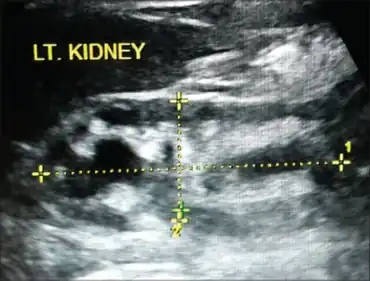

| Kidney has moderate hydronephrosis with scarring at lower pole, consistent with reflux nephropathy | |

It is diagnosed by micturating cystography; scarring can be demonstrated by ultrasound or DMSA.